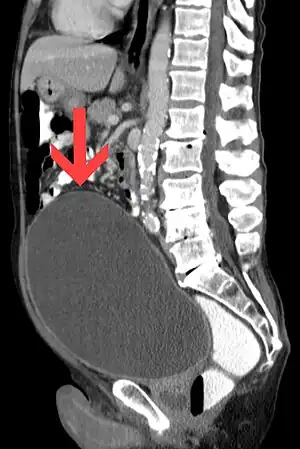

| CT scan in the sagittal plane which reveals a greatly enlarged urinary bladder caused by urinary retention, a condition which often leads to overflow incontinence. | |